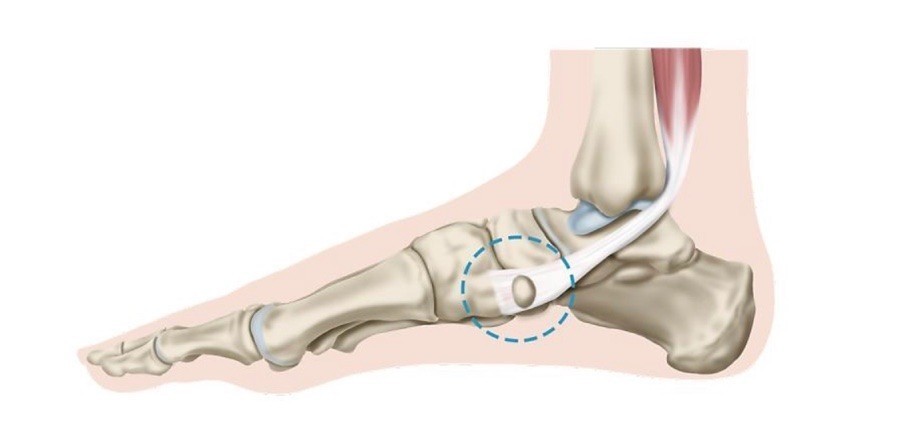

발바닥에 있는 족저근막에 손상이 발생해서 염증과 통증을 일으키는 질환인데요. 흔히 발뒤꿈치 통증을 일으키는 대표적인 질환입니다. 평균 발병 연령은 45세 정도이고, 여성이 남자보다 2배 정도 많이 발생해요. 족저근막은 발뒤꿈치 뼈에서 발바닥 앞쪽으로 이어진 두꺼운 섬유 띠인데요. 이는 발바닥의 탄력과 아치 모양을 지속시켜 줍니다. 발을 들어 올릴 수 있게 해 주며 발에 가해지는 충격을 흡수하기 그리하여 보행 시 매우 주요한 역할을 해요.